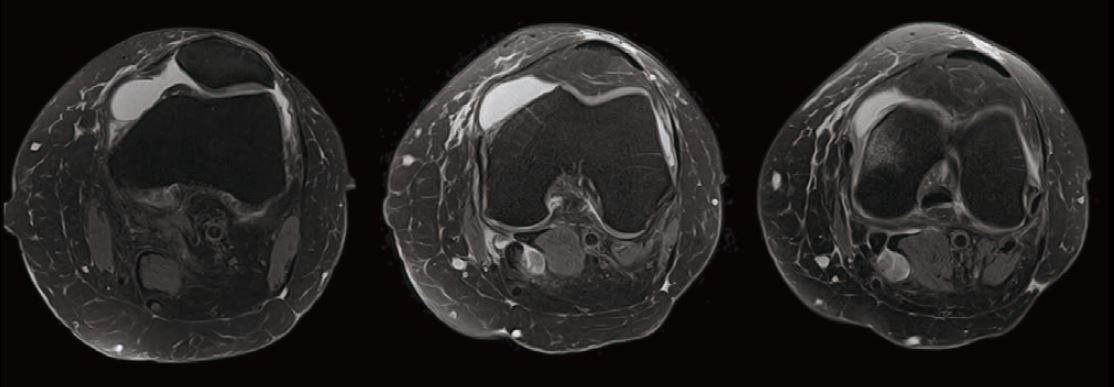

Випадок 1. Велике коліно

Жінка 67 років скаржиться на постійний медіальний біль у коліні.

• Відносно рясний внутрішньосуглобовий випіт.

• Остеоартритне ураження стегново-гомілкового суглоба в медіальній частині зі змінами субхондральної кістки, що може відповідати стресовому перелому.

• Дегенеративна сторона заднього рогу медіального меніска.

Рис. 4 Axe FSE PD FS, товщина зрізу 3 мм, роздільна здатність 0,6 мм.